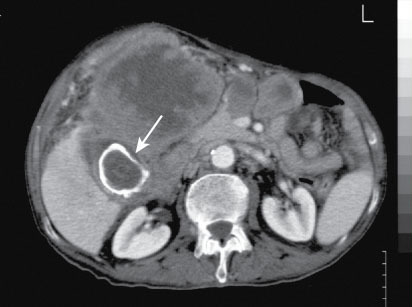

Porcelain Gallbladder

thickened gallbladder wall with a rim of patchy calcification